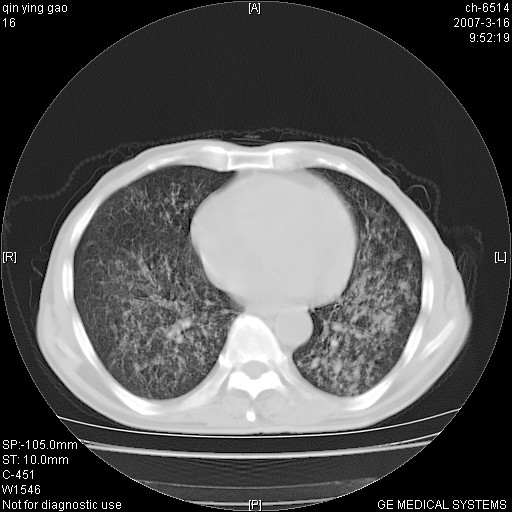

男,64岁.乏力2个月,畏寒、发热1月余。体重下降。血沉加快,白细胞不高。

双肺可见大小不等结节状密度增高影,密度不均,分布不均(双肺上叶为著),亚急性血行播散性肺结核.

(本例特征:以大小不等结节为主,主要分布在双上肺,并部分病灶融合成较大结节,期间搀杂诸多细小结节。从病灶特点与分布形式分析,更趋向于感染。)

男,64岁.乏力2个月,畏寒、发热1月余。体重下降。血沉加快,白细胞不高。 双肺可见大小不等结节状密度增高影,密度不均,分布不均(双肺上叶为著),亚急性血行播散性肺结核.

以双肺上叶为主的弥漫型斑片状密度增高影,边界欠清晰,其中伴有钙化灶,病人有发热史,首先考虑感染性病变:1特殊类型感染,2结核。建议治疗后随诊复查,除外肺泡癌

两中上肺见有广泛分布大小不一的结节灶及斑片状影,部分融合,双下肺未见异常密度影,纵隔无明显肿大淋巴结,血沉加快,白细胞不高,首先考虑结核。 建议结合ppd检查或痰培养排除其他非特异性炎症。

中上肺野密布棉团状影,以胸膜下区为界,边缘模糊,可能是小叶或腺泡渗出及实变。全肺野弥漫分布网线样影及细小粟粒样影,可能是细支气管炎及间质内炎症。综合分析应首先考虑气道播散性感染,而肺内多处斑点性钙化,强烈提示陈旧结核复发并支气管播散。建议详细讯问病史